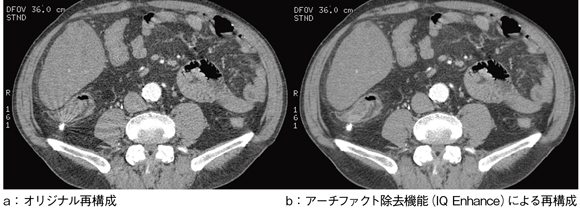

この高速性を実用化するには,画質との両立が不可欠となるため,Optima CT660では,Clear View Technologyの中で,高速撮影と高画質を両立される機能“IQ Enhance”を搭載した。これは,マルチスライス特有のハイピッチデータ収集時に発生するウィンドミルアーチファクトを効果的に除去する機能で,プロジェクション領域において収集されたデータをいったんボリュームとしてとらえ,統計的に連続性のあるノイズ(パターン化されたノイズ)成分を選択的に除去する効果を発揮する(図2)。この機能により,ワイドビームでのハイピッチヘリカルスキャン時のアーチファクトが改善され,腹部領域での高速スキャンの実用化が可能になると期待できる。

図2 ウィンドミルアーチファクト除去効果